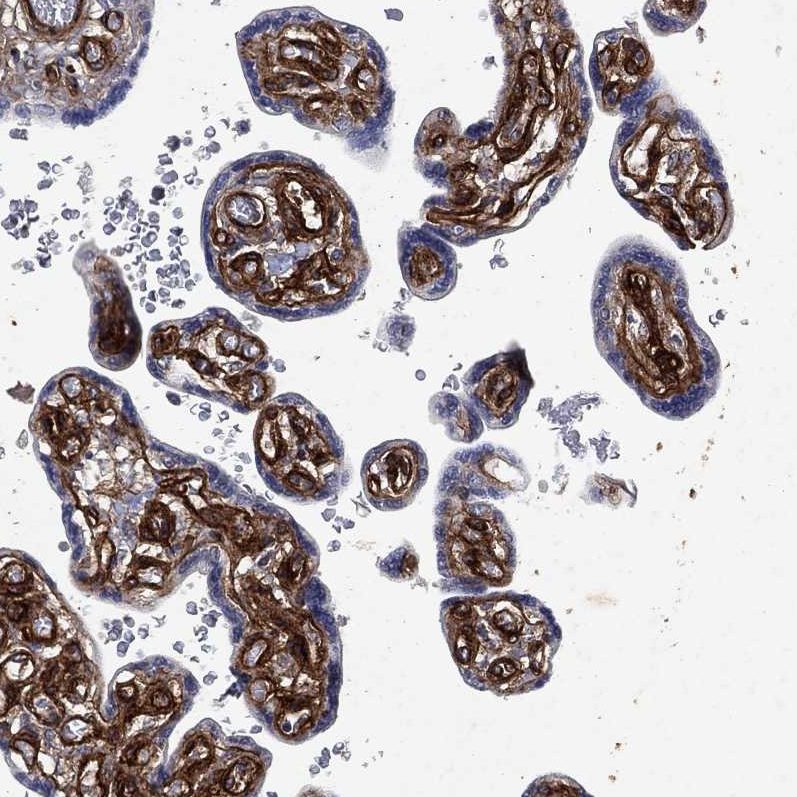

Immunohistochemical staining of human placenta shows strong membranous positivity in endothelial cells.